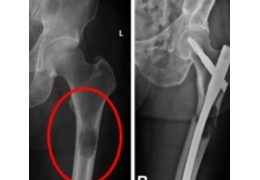

Long bone skeletal metastases are common in theUS, with more than 280,000 new cases every year.Clinical dilemma: whether the metastatic tumor hasweakened the bone

sufficiently such that apathological fracture is imminent. To answer thatquestion, physicians rely primarily on MirelsCriterion which has been criticized by MDsregarding its

ability to predict fractures. Simfini-TUMOR provides a reliable risk of fractureassessment to address this clinical dilemma. Hence.fewer unnecessary surgeries need be performed.